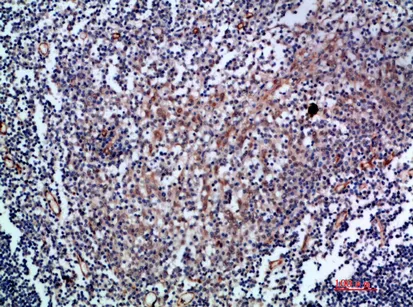

CD83 Rabbit Polyclonal Antibody

Cat: APRab08469

Size1:50μl Price1:$118

Size2:100μl Price2:$220

Size3:500μl Price3:$980

Size2:100μl Price2:$220

Size3:500μl Price3:$980